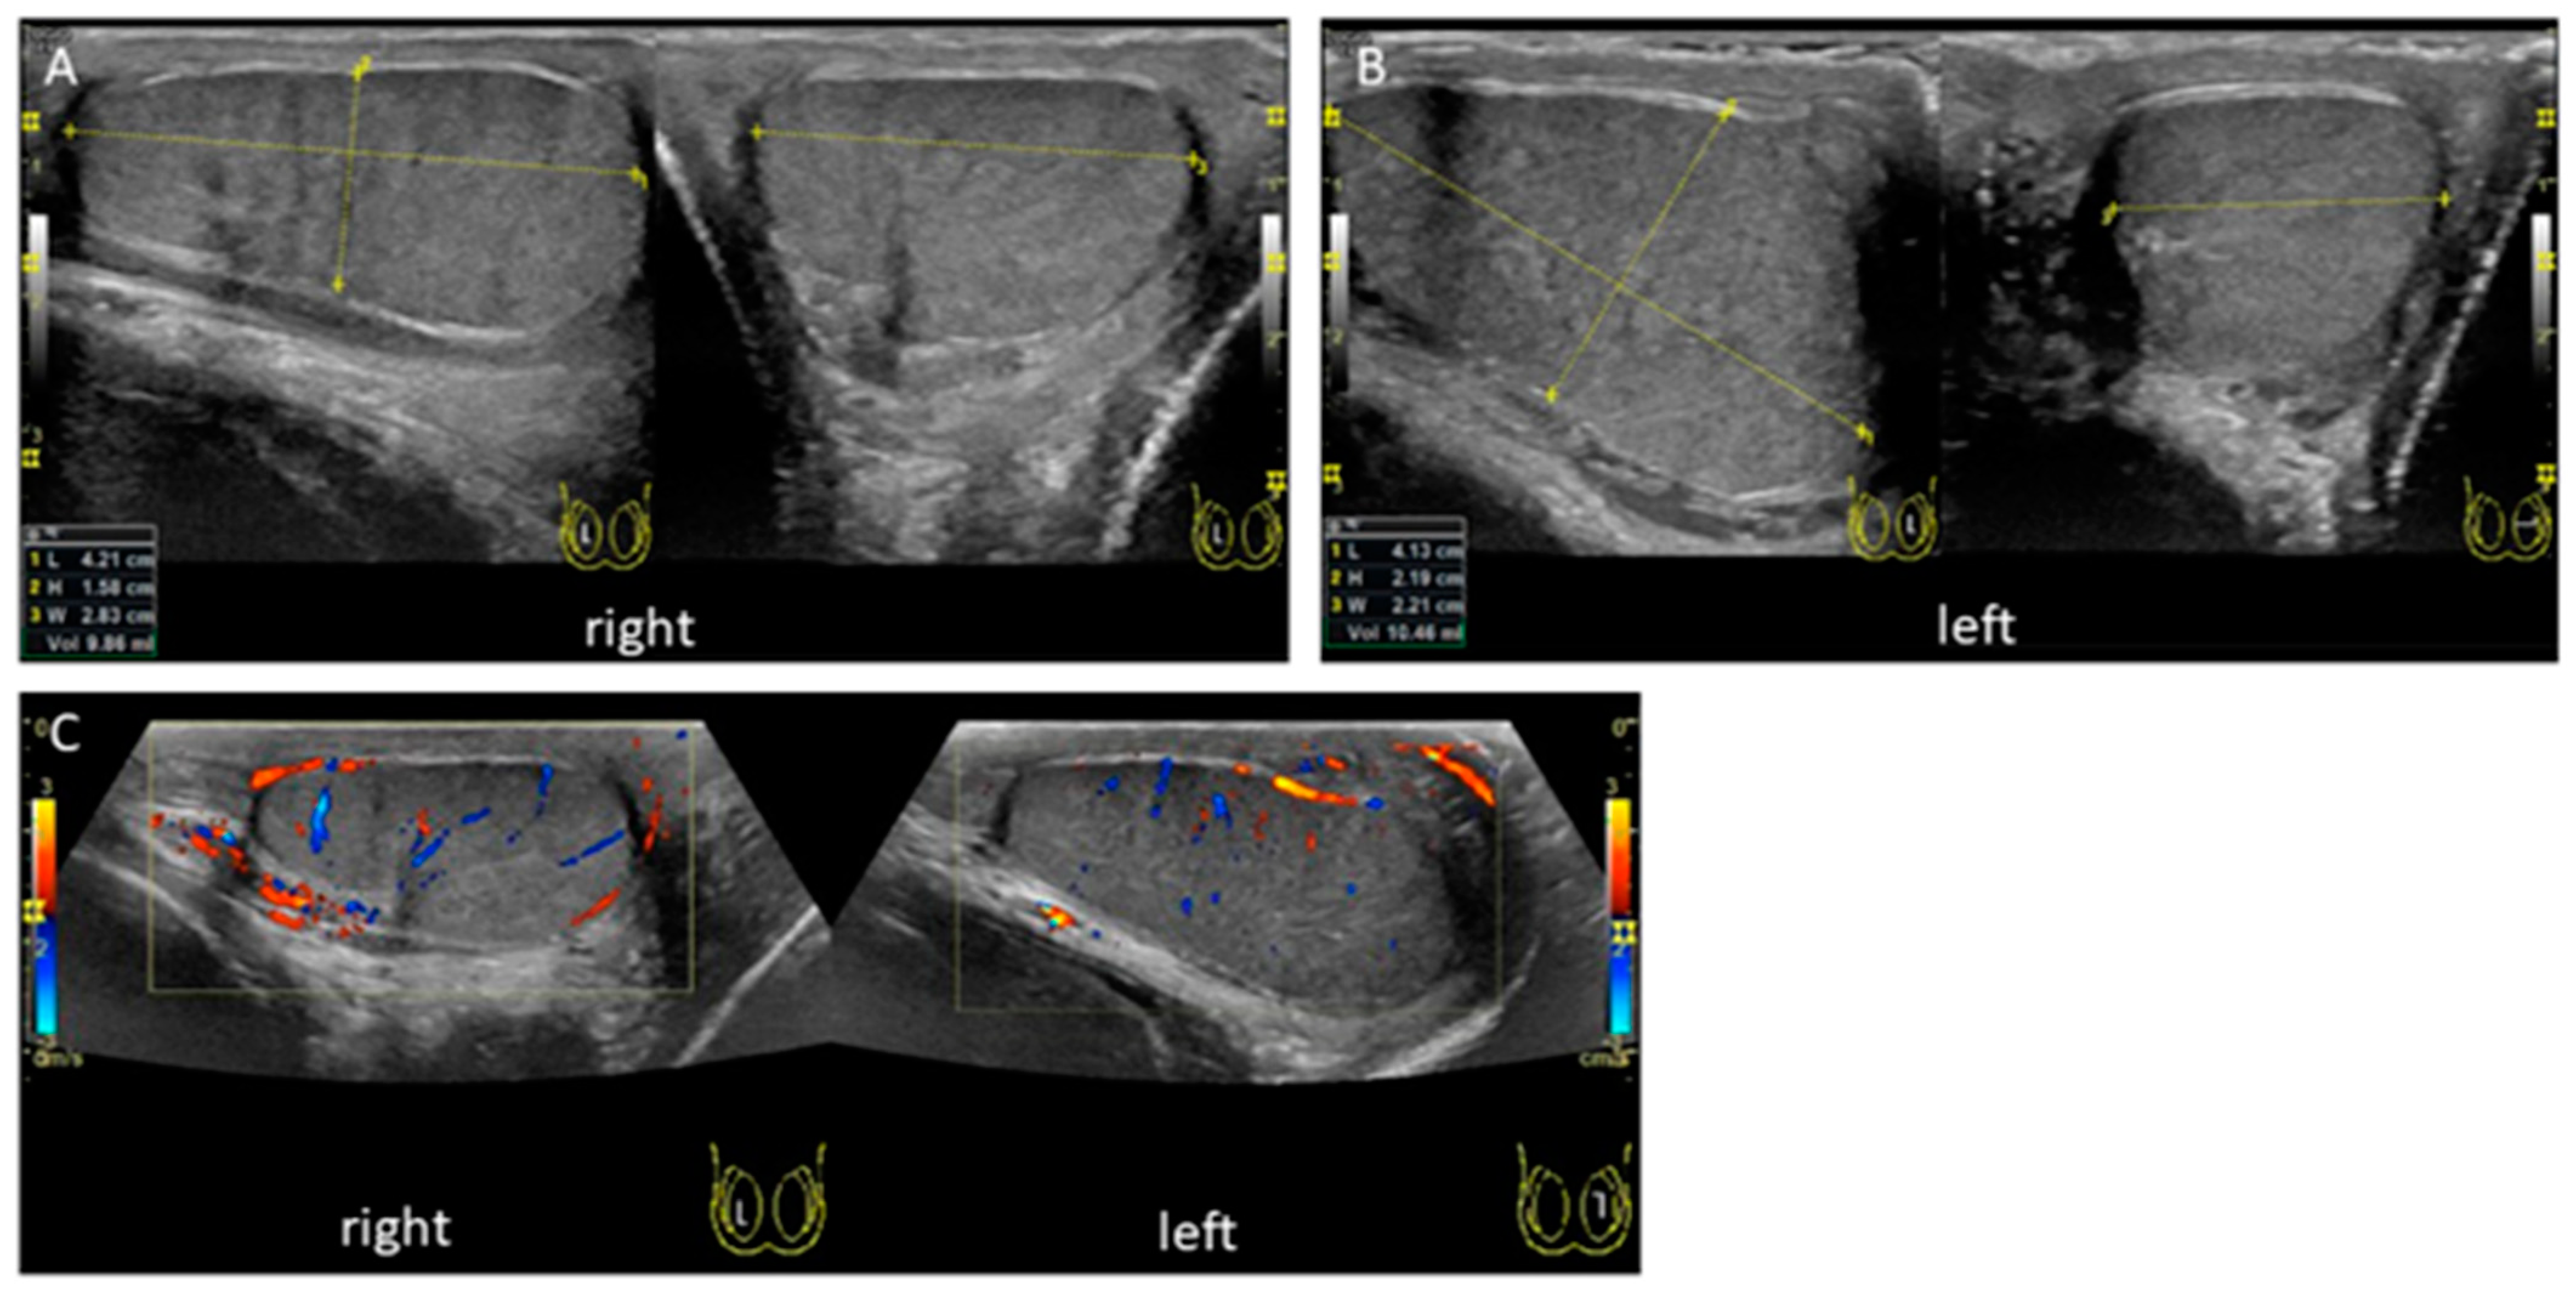

2. Case Presentation